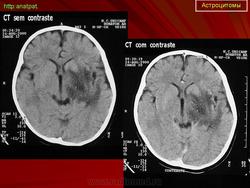

ГМ. Астроцитома. +

Астроцитома.